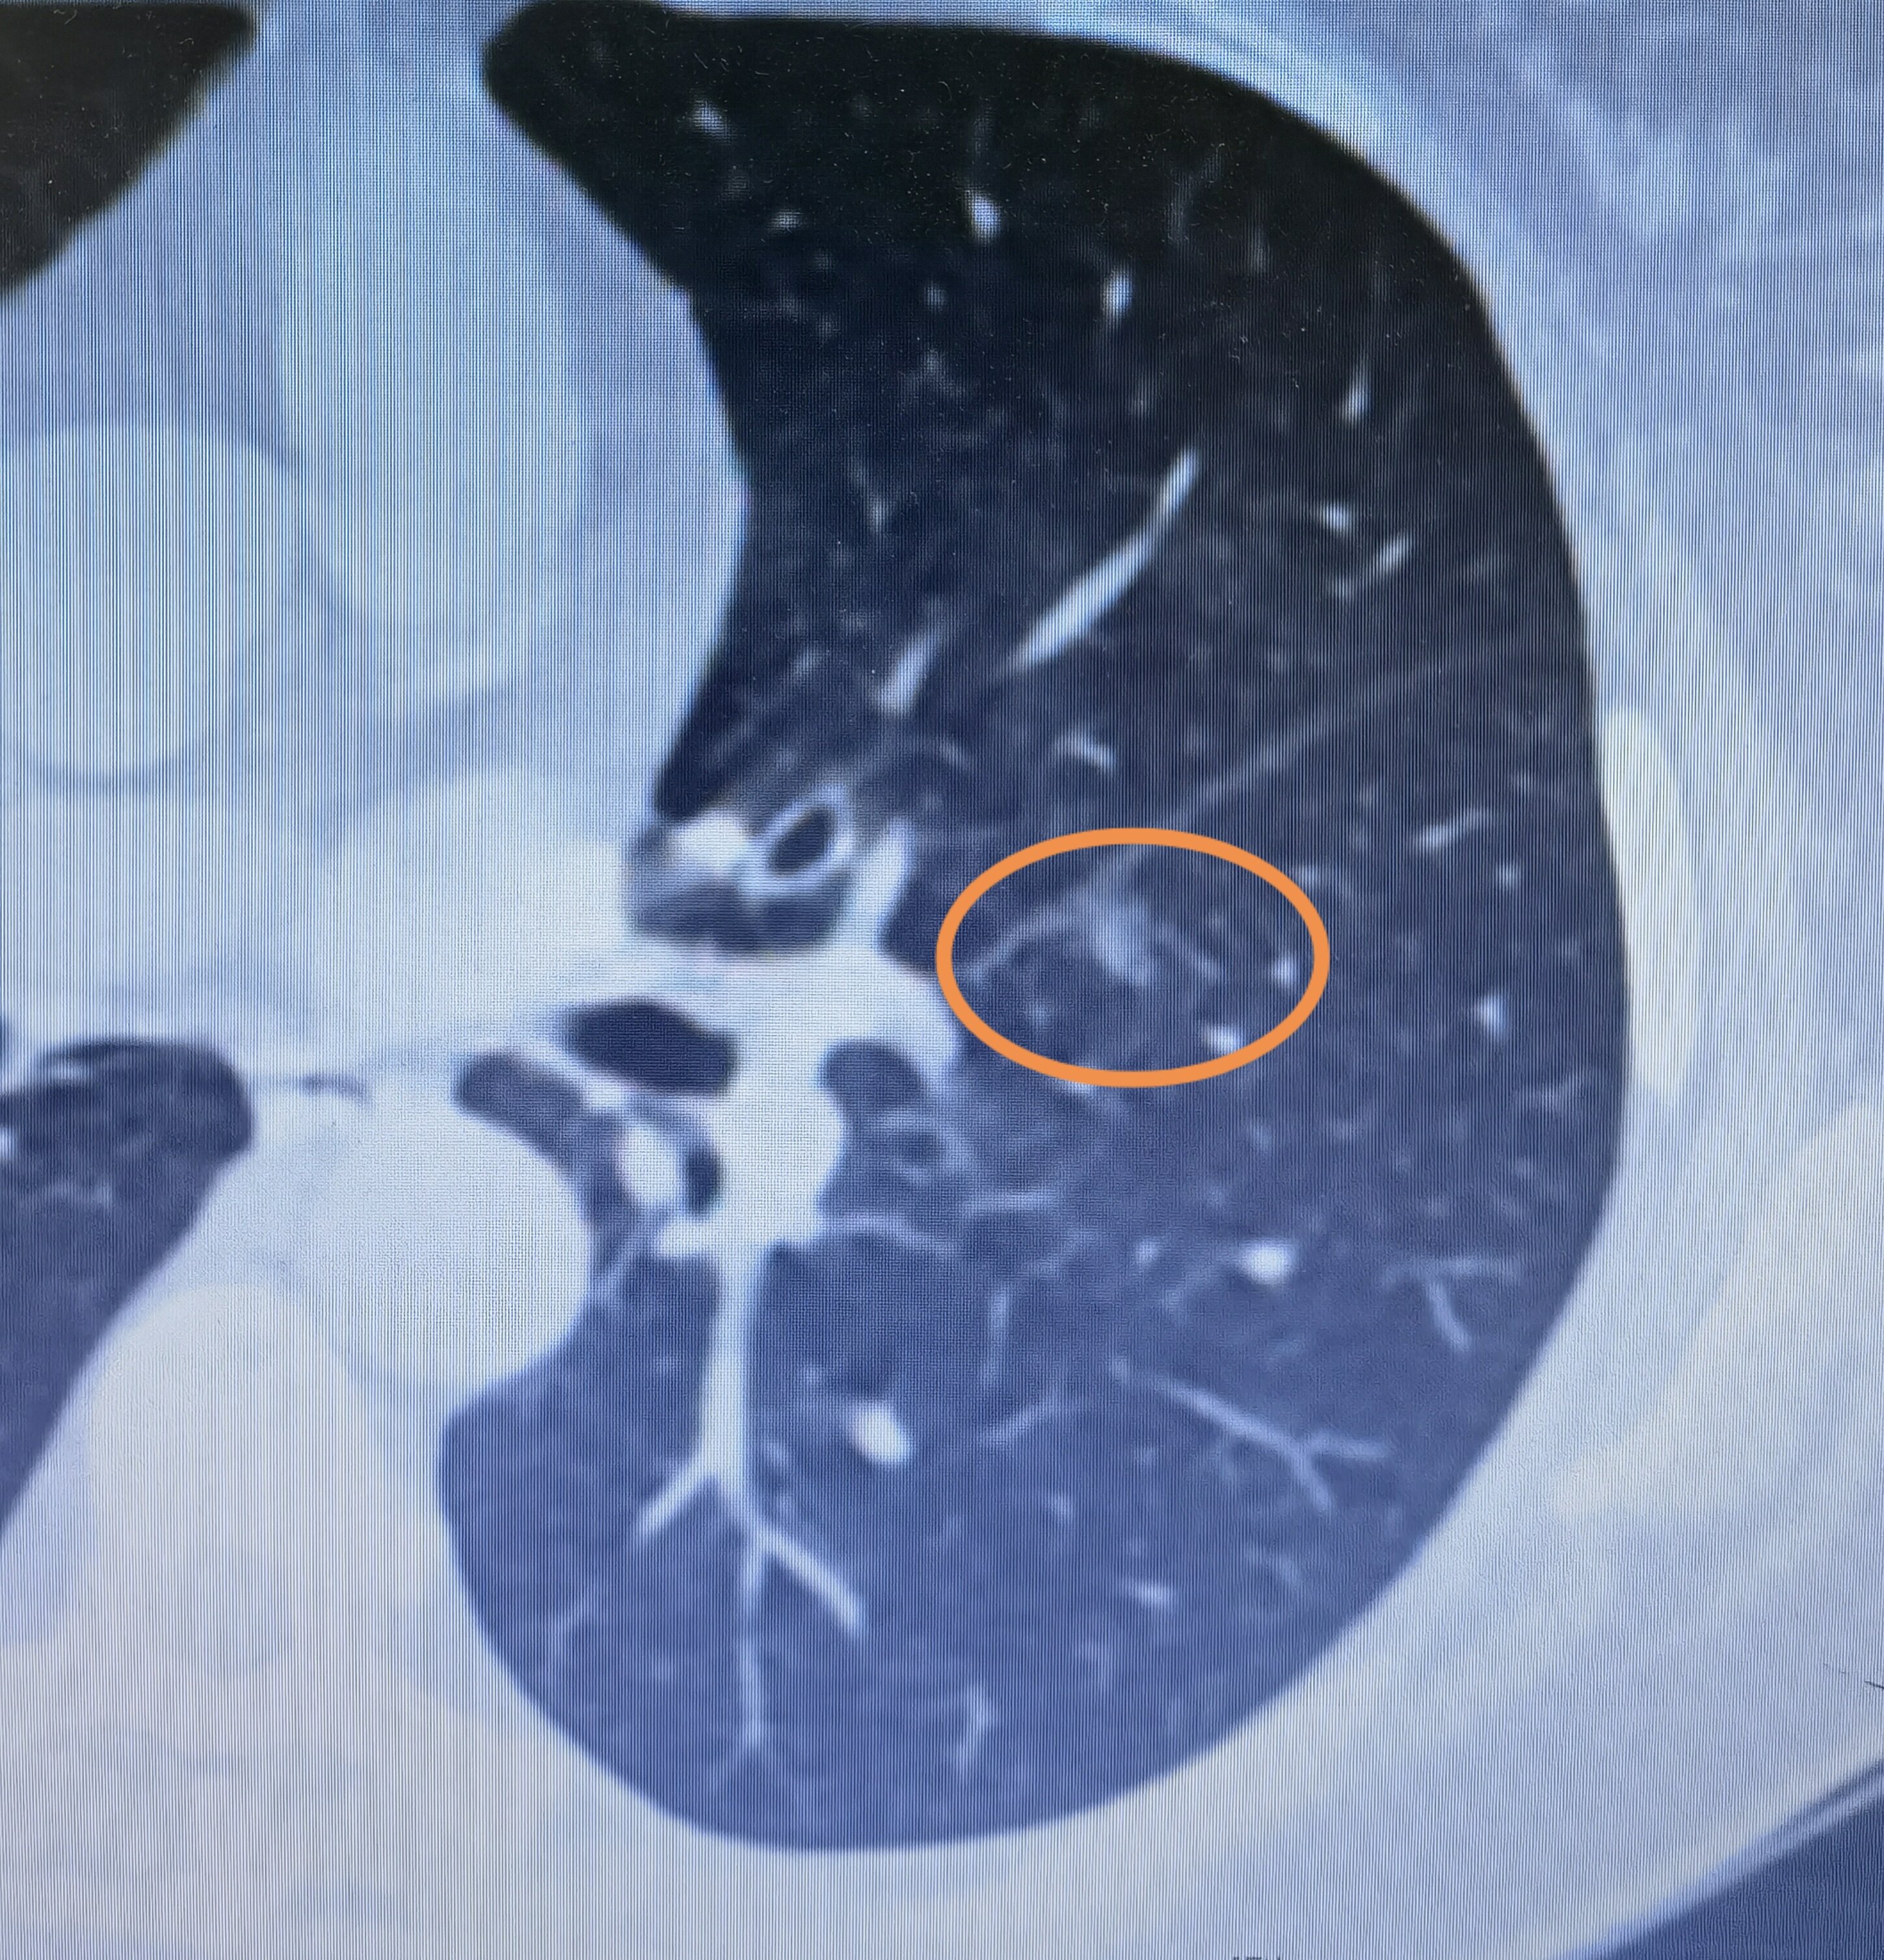

右肺上叶结节

右肺上叶结节,肺部结节

右肺上叶尖段多发小结节是不是肺癌

右肺上叶毛玻璃结节,不典型腺瘤样增生?

10问肺小结节

此消彼长的肺结节会是恶性的吗

磨玻璃结节